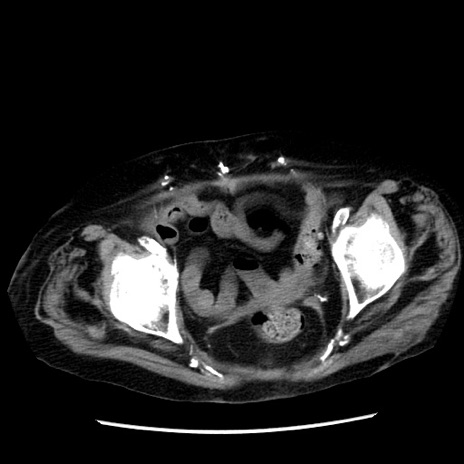

症例14(横断像)

【症例】 90歳代女性

【主訴】 腹痛・嘔吐

【現病歴】今朝から左側腹部痛を認めた。 経過観察していたが、嘔吐を認めたため来院。

【既往歴】 子宮癌術後

【身体所見】 意識清明、BP 127/54mmHg、P 98bpm Sp02 95%(RA)、BT 35.8°C、腹部平坦・軟腸ぜん動音聴取良好、右下腹部圧痛(+) 反跳痛なし

【データ】WBC 9800、CRP 0.46